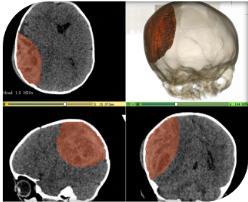

据了解,该患儿从床上不慎摔落致头部受伤,未引起家长重视,随后出现呼叫不醒,伴有恶心呕吐,精神萎靡等症状。遂来我院急诊儿科就诊,急查头颅 CT 提示,颅内巨大血肿,中线结构移位,脑组织受压明显。

入院时患儿病情危重,已陷入昏迷,重度贫血貌,双瞳孔反射迟钝,生命危在旦夕。会诊后,立即转入神经外科一病区救治。考虑患儿年龄小、病情重、手术及麻醉风险极大、可能预后不良等因素,神经外科一病区迅速成立救治小组,与麻醉科、重症医学科、儿科、泌尿外科、输血科等多学科联合,克服重重困难,急诊在全麻下行开颅手术,清除血肿约 130ml(该患儿体重约 7.5kg)。

术后骨瓣还纳,为大程度减小手术切口及不影响患儿以后颅骨的生长发育,采用精准影像融合技术定位,以及可吸收颅骨锁固定骨瓣,手术顺利。术后在重症医学科严密观察患儿意识及生命体征,48 小时后患儿各项生命体征平稳,转回神经外科一病区继续治疗。

经过医护人员 2 周的专业治疗和精心护理,患儿病情恢复良好,术后复查头颅 CT显示:血肿完全清除,中线恢复居中,骨瓣回位良好,现已治愈出院。